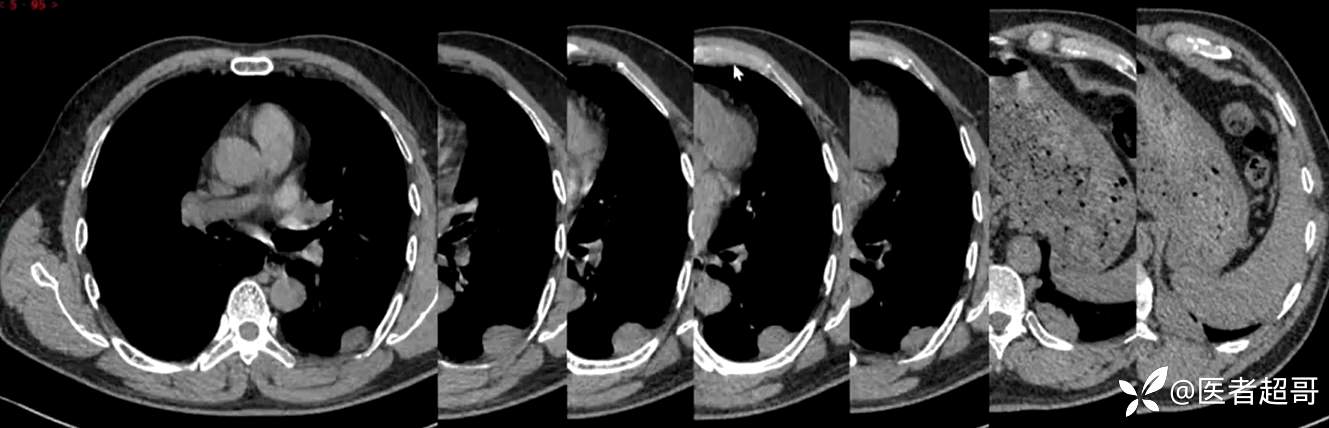

现病史:患者5月前因咳嗽、咳痰于当地医院就诊,完善胸部CT提示:胸膜多发占位,期间患者无胸闷、气紧、咳嗽、咳痰、心慌等不适,患者于我院门诊行胸部CT提示:左下胸膜增厚并见多个软组织密度结节影局限性凸起,较大者大小约3.5x2.2cm,增强扫描呈持续性轻度强化,考虑肿瘤性病变可能性大;门诊遂以:胸膜肿瘤收入我科。